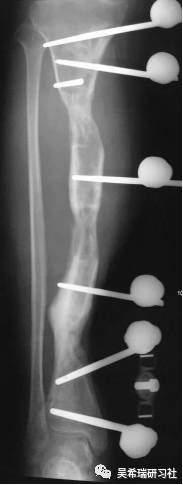

手术后40天外地转来胫骨外露感染骨坏死20cm胫前皮肤缺损腘动脉断裂腓总神经损伤足下垂

TIPS:第一次手术  清除病灶抗生素骨水泥填塞。远端整块水泥包裹外露骨质,近端连珠以便骨搬移钢丝克氏针张力缝合皮肤5天后下地部分负重走路联合骨牵引纠正足下垂15天后去除跟骨骨牵引针

TIPS:骨水泥40天后去除,半开放植骨因为有皮肤缺损,用骨水泥做成瓦片闭合伤口自体优质松质骨(如图)(半开放植骨的典范)皮肤采用了钢丝牵张闭合骨搬移+半开放植骨植骨后一个月去除瓦片骨水泥,创面新鲜钢丝克氏针张力闭合伤口加游离植皮继续骨搬移修整入院3个月腓总神经恢复